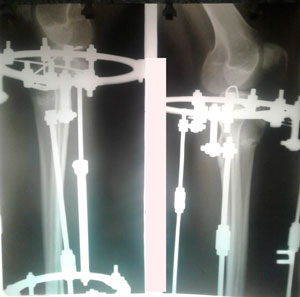

перед крутками

на фиксации

Ножки и рентген перед снятием аппаратов.